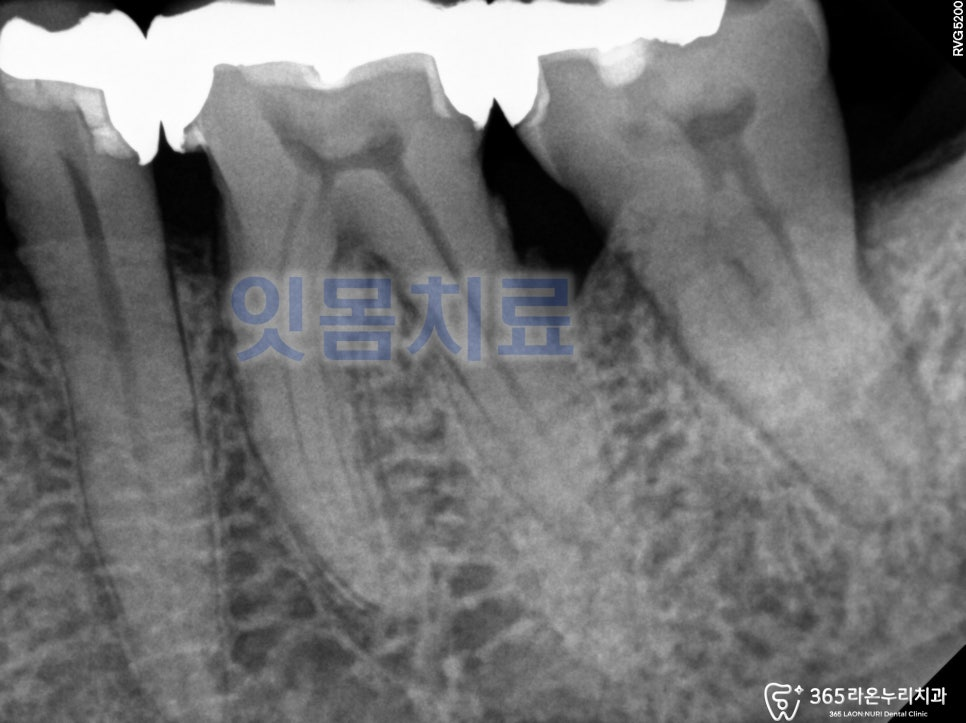

신장2동 치과 에서

엑스레이 사진을 보면

25.1.24

치아가 없고,

치조골이 녹아 제대로

지지를 못받고 있는 어금니를

볼 수 있습니다.

신장2동 에서 발치된 공간을 보면

치조골이 얇아져 있어

임플란트 픽스처 식립이 어려워 보입니다.

상악동 뼈이식을 통해 픽스처가 들어갈 수 있는

뼈를 만들어 주고 어금니 식립을

진행 해야 됩니다.